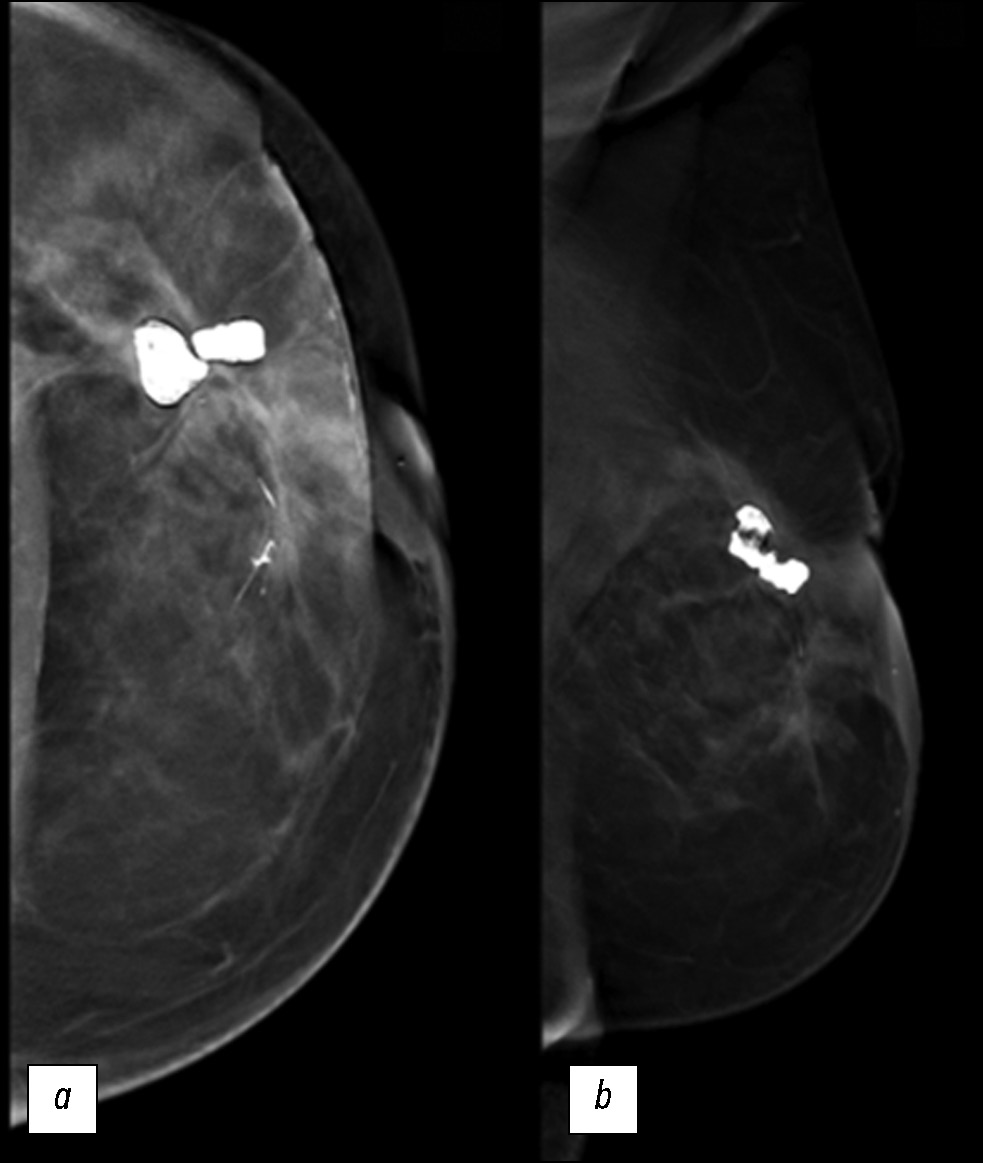

Navigating secondary breast angiosarcoma: a case report

Abstract

We describe a rare case of secondary breast angiosarcoma in a 72-year-old woman with a history of breast cancer who presented to our clinic with a painless palpable mass in the outer upper quadrant of the left breast. The diagnosis required a multidisciplinary approach involving a senologist, anatomopathologist, and oncologist. Imaging modalities such as mammography, ultrasonography, and magnetic resonance imaging made it possible to assess the extent of the tumor, lymph node involvement, and distant metastases. The diagnosis was confirmed by a tissue biopsy. Herein, a rare case is presented, with the main educational purpose of describing the clinical presentation and complex diagnostic evaluation and discussing the differential diagnosis and management. Indeed, secondary mammary angiosarcoma is a rare and aggressive neoplasm, and understanding its unique features is essential for clinical decision-making and patient outcomes. The tumor has a worse prognosis because of its late diagnosis, higher risk of rapid distant spread, and limited treatment options. Such cases require close monitoring, aggressive strategies, and supportive care.